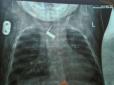

Думали, що бронхіт: В Одесі лікарі врятували немовля, яке проковтнуло пружину (фото)

В обласній дитячій клінічній лікарні Одеси медики врятували життя немовляті шести місяців, яке проковтнуло пружину від заколки для волосся. Лікарі витягли сторонній предмет із стравоходу. До цього дитину помилково лікували від "бронхіту" в районній лік...